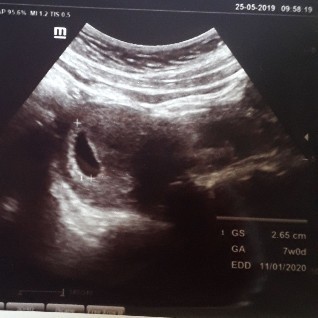

Bun aku bingung deh, hptp ku kan 15april trus aku emang udah cek testpack positif udah kebidan juga 17mei kemarin dan bidan bilang 4week, trus tadi barusan aku dari dokter obgyn dan di usg hasil usgnya udah 7week masa bun? terus juga tadi sama dokternya di cek usg biasa masih berupa kantong tapi ukuran kantongnya udah 2,65cm mau 3cm gitu, kata dokternya 2minggu lagi suruh kontrol buat cek lagi kalo masih berupa kantong katanya mau dikurret? Tadi sih dokter ku kasih 3 kemungkinan bun, yg pertama emang janin belom keliatan, kedua kaya ada kista samar2, dan ketiga hamil kembar anggur jadi 1didalem rahim 1lagi diluar rahim?? Menurut bunda bunda disini aku perlu second opinion atau tetep jalanin proses dokter yg ini? Aku syok banget bun, memang sih sama dokternya tadi dikasih obat kaya folavit sama penguat janin tapi tetep aja aku syok banget bun denger kata kuret apalagi ini kehamilan yang pertama???